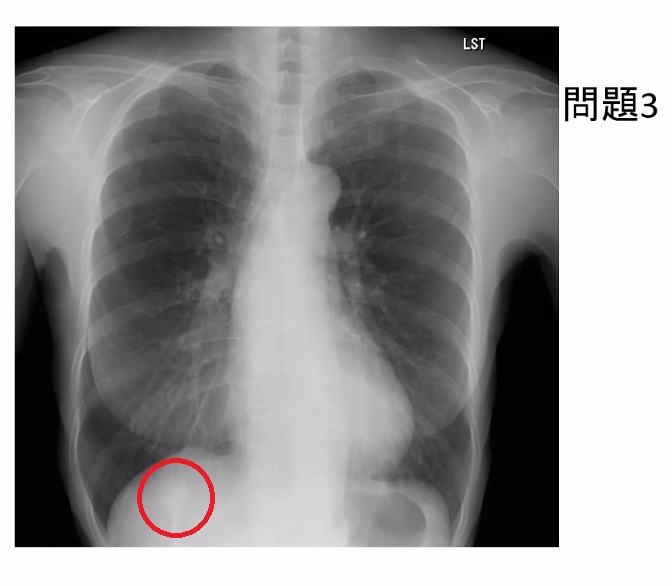

正解はこちらです。

この症例は肺がんだったそうです。見落としやすい場所を頭に入れて、注意深く胸部X線を見ていきましょう。